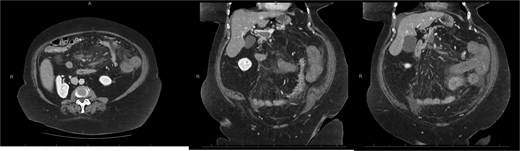

A 76-year-old female with a 3-day history of left upper abdominal pain, vomiting, and haematochezia. Her history included pulmonary embolism, multiple deep vein thromboses, with no ongoing anticoagulation, and an open partial colectomy for complicated diverticulitis a decade earlier. On admission, she was afebrile but tachycardic and showed localized tenderness in the left hypochondrium. Laboratory revealed leucocytosis with a white blood cell count (WBC) of 12 G/L, elevated C-reactive protein (CRP) of 46 mg/L, and hyperlactatemia of 2.6 mmol/l. Enhanced computed tomography (E-CT) revealed jejunal venous ischemia in the left upper quadrant, secondary to extensive porto-mesenteric thrombosis with reduced bowel wall enhancement, distention, and free intraperitoneal fluid (Fig. 1). She was managed conservatively with unfractionated heparin (UFH) with a bolus of 5000 U/l followed by 30 000 U/l/24 h (target INR 0.35–0.7), Piperacillin-Tazobactam, and bowel rest. After 48 h of monitoring in the intensive care unit (ICU), she exhibited marked biological and clinical improvement. E-CT on the third day showed restored bowel wall enhancement and stable porto-mesenteric thrombosis (Fig. 2). She was discharged on therapeutic low molecular weight heparin (LMWH) with enoxaparin sodium 120 mg every 12 h. At the 3-month follow-up, E-CT revealed near-complete thrombus resolution, without intestinal sequelae (Fig. 3).

Abdominal E-CT of the first patient at admission. The white arrows indicate extended porto-mesenteric thrombosis, while the dashed arrows reveal jejunal venous ischemia with a lack of bowel wall enhancement, bowel distension, and free fluid.